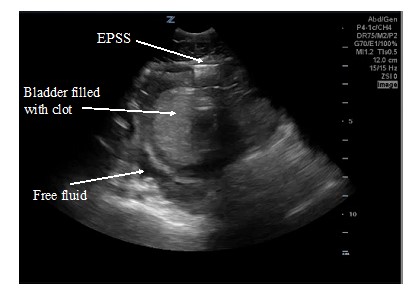

An 18-year-old male was brought in by EMS with a penetrating stab wound to his left buttock from an unknown weapon. Blood was oozing from the stab wound entry site, but he was hemodynamically stable. Shortly after arrival to the emergency department, he developed frank hematuria. An initial FAST exam revealed a large clot within the bladder walls (Fig. 1) but was negative for intraabdominal free fluid. A large hematuria catheter was placed by Urology to evacuate this clot. CT and CT angiogram of the abdomen and pelvis revealed active bleeding within and adjacent to the left posterior bladder wall, as well as a clot filled bladder and a deep pelvic hematoma displacing the rectum. A CT cystogram revealed no filling defect within the distal ureters or extravasation of contrast to suggest intra- or extra-peritoneal bladder rupture. After CT imaging, Urology copiously irrigated the bladder with normal saline to remove the clot. During irrigation, the patient developed significant abdominal pain and distension. A repeat FAST exam was performed revealing free fluid in the right upper quadrant (Fig. 2), left upper quadrant (Fig. 3), and pelvis (Fig. 4). The pelvic view also revealed an enhanced peritoneal stripe sign (Fig. 4) suggesting pneumoperitoneum.

The evaluation of adult patients usually starts with the RUQ view, since this is the location that free fluid collects first, followed by the LUQ view. If there is difficulty identifying structures or spaces in the upper abdominal views, have the patient inhale deeply which may help bring the liver/spleen/heart down into view rather than looking through intercostal spaces with the effect of rib shadowing. It is important to visualize both kidneys in their entirety as blood may collect only at the inferior or superior poles. A more posterior placement of the probe may be necessary to aim towards the kidneys to obtain a complete view. In the suprapubic view, free fluid may be visualized either posterior or adjacent to the bladder. It is often necessary to decrease the far field gain (time gain compensation) to minimize posterior acoustic enhancement artifact and improve visualization of free fluid. Fluid in the bladder optimizes this view, and an empty bladder may make it difficult to assess the suprapubic area for free fluid. In addition, a Foley catheter may make it difficult to distinguish the bladder from surrounding free intraperitoneal fluid. (Fig. 4) In younger patients, consider starting with the suprapubic view, as this is the most dependent portion of the abdominal cavity in children.

The enhanced peritoneal stripe sign (EPSS)

The EPSS has been described as a specific sonographic sign of pneumoperitoneum. The peritoneal stripe is normally seen as a thin echogenic line at the interface of the anterior abdominal wall and adjacent intraperitoneal fluid. In patients with pneumoperitoneum, small amounts of free air produce focal enhancement and apparent thickening of the peritoneal stripe (EPSS). (Fig. 4) Larger amounts of air may produce both the EPSS as well multiple reverberation artifacts, appearing as horizontal stripes and echogenic lines with comet tails.12,13

Figure 4. Pelvic view of the repeat FAST. Free intraperitoneal air is seen as the enhanced peritoneal stripe sign (EPSS). Anechoic free fluid is also seen posterior to the bladder.